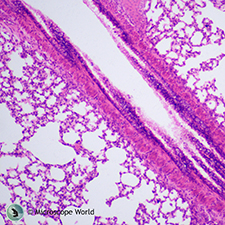

| Loose Connective Tissue | Mammal Lung | |